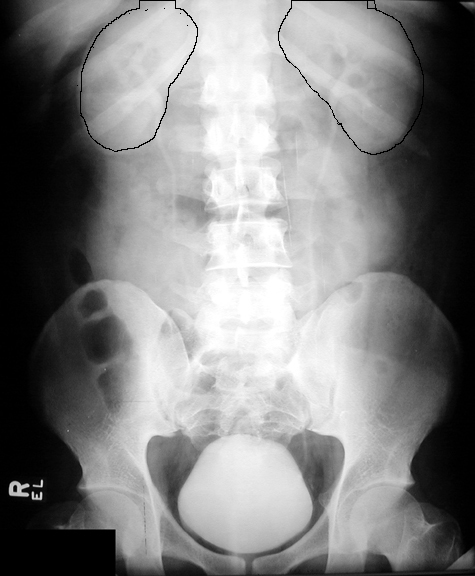

Appreciate the shape of kidneys. Click the image for labeling.